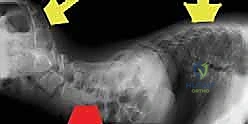

هذا النوع من الجنف ليس مجرد انحناء جمالي أو بسيط في العمود الفقري؛ إنه تشوه هيكلي متسارع يؤثر بشكل عميق على كل جانب من جوانب حياة الطفل. مع تطور الانحناء، يفقد الطفل القدرة على الجلوس بشكل مستقيم في كرسيه المتحرك، مما يؤدي إلى تقرحات جلدية مؤلمة. الأسوأ من ذلك، يضغط العمود الفقري الملتوي على التجويف الصدري والبطني، مما يعيق تمدد الرئتين ويسبب صعوبات تنفسية خطيرة، ويضغط على المعدة والأمعاء مما يعيق التغذية والهضم.

ميلان الحوض (Pelvic Obliquity): التحدي الأكبر

أحد أهم الفروق بين الجنف العادي والجنف العصبي العضلي هو امتداد التشوه ليشمل الحوض. يُعرف هذا بـ "ميلان الحوض". عندما يميل العمود الفقري، فإنه يسحب الحوض معه. نتيجة لذلك، يصبح أحد جانبي الحوض أعلى من الآخر. عندما يجلس الطفل، يتركز كل وزنه على عظمة واحدة في الحوض (الحدبة الإسكية) بدلاً من توزع الوزن بالتساوي. هذا يسبب ألمًا مبرحًا، وتقرحات فراش (Bedsores) خطيرة، ويجعل من المستحيل على الطفل الجلوس دون دعم كامل.

- صعوبات التنفس المتزايدة: مع التواء القفص الصدري، تتقلص المساحة المتاحة للرئتين، مما يؤدي إلى التهابات رئوية متكررة ونقص في مستويات الأكسجين.

الجراحة هي الخيار النهائي والفعال لمعظم حالات الجنف العصبي العضلي المتقدمة، خاصة عندما يتجاوز الانحناء 50 درجة، أو عندما يترافق مع ميلان شديد في الحوض يمنع الجلوس.